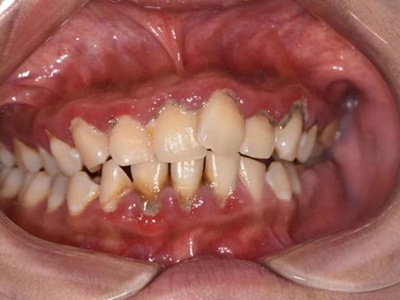

急性坏死性溃疡性龈炎症状图片

急性坏死性溃疡性龈炎起病急,病程短,常为数天至1-2周,以龈乳头和龈缘的坏死为其特征性损害,尤以下前牙多见,初起时龈乳头充血水肿,个别龈乳头顶端可发生坏死性溃疡,上覆有灰白色坏死物,中央凹下如火山口状。龈缘如虫蚀状,坏死区出现灰褐色假膜,擦去后可见出血创面。龈乳头被破坏后与龈缘成一直线,如刀切状。病损一般不波及附着龈,患处牙龈极易出血,疼痛明显并有腐败性口臭。

重症患者可有低热、疲乏等全身症状,并可伴有下颌下淋巴结肿大和压痛。有的患者可能进展为坏死性龈口炎、坏死性溃疡性牙周炎等疾病,从而导致牙周袋形成、牙槽骨吸收和牙齿松动。

对于急性坏死性溃疡性龈炎,可先轻轻去除局部坏死组织,去除大块龈上牙石,使用过氧化氢溶液擦拭、冲洗和含漱。必要时在清洁后局部涂布抗厌氧菌制剂,全身给予维生素C、蛋白质等支持疗法。重症患者可口服甲硝唑或替硝唑,对于不良诱因要及时去除。急性期过后可采取洁治、刮治以及必要的牙周手术。